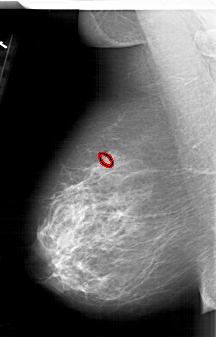

A_1626_1.LEFT_MLO

LEFT_MLO LINES 6391 PIXELS_PER_LINE 4096 BITS_PER_PIXEL 12 RESOLUTION 43.5 OVERLAY

FILE: A_1626_1.LEFT_MLO.OVERLAY

TOTAL_ABNORMALITIES 1

ABNORMALITY 1

LESION_TYPE CALCIFICATION TYPE PLEOMORPHIC DISTRIBUTION CLUSTERED

ASSESSMENT 4

SUBTLETY 2

PATHOLOGY MALIGNANT

TOTAL_OUTLINES 1